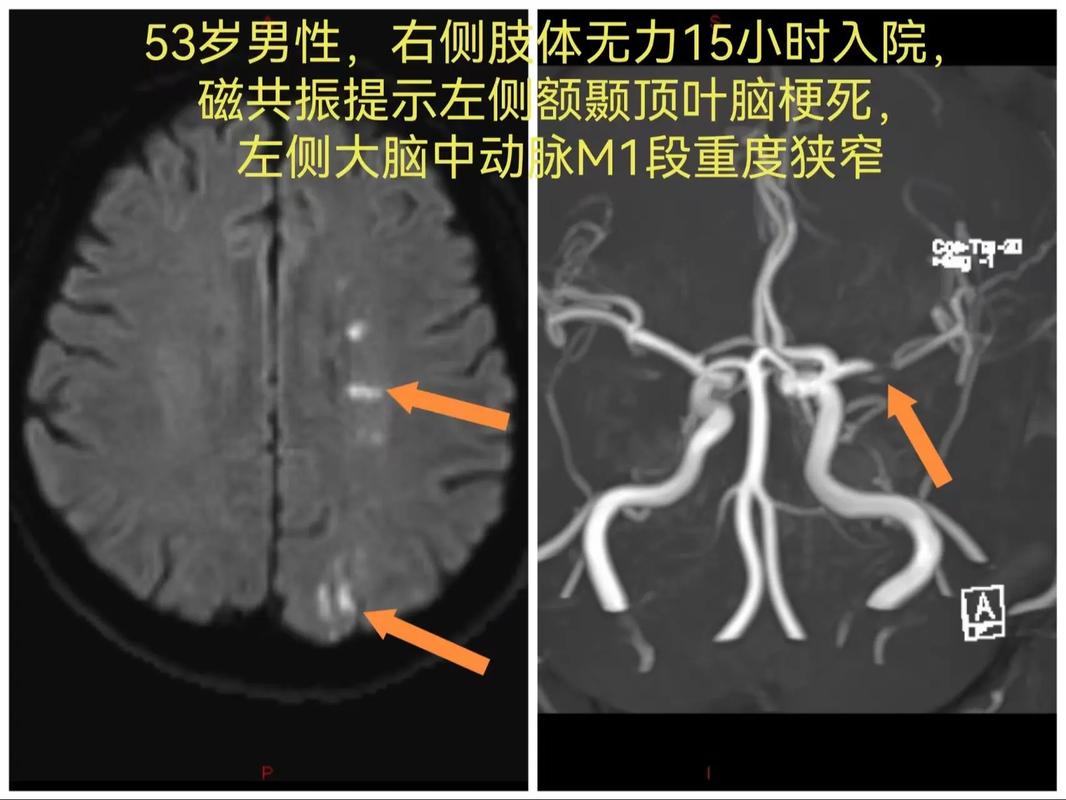

- CTA(CT血管造影)或MRA(磁共振血管造影):能更清晰地显示颅内血管的情况,评估狭窄范围和程度,医生会根据情况建议复查间隔。